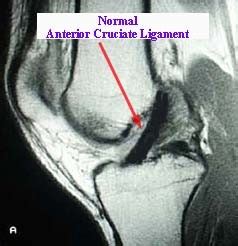

Anterior Cruciate Ligament Tear Treatment & surgery | DR. RAJ KANNA

MRI of ACL Tear

ACL Tear MRI vs Normal

What Does a ACL Tear Look Like On MRI

Intact ACL MRI